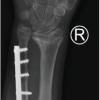

A representative example of Case 1 is illustrated in Figures 1–6. The preoperative radiograph is shown in Figure 1, while Figure 2 demonstrates the MRI findings confirming avascular necrosis of the lunate. Figures 3–5 depict the immediate postoperative radiographs and sequential follow-up images up to 1 year. Figure 6 shows the final clinical photograph, demonstrating a good functional outcome.

Figure 1: This is an example of case 1, which shows a pre-operative image of anteroposterior, oblique, and lateral radiographs revealed lunate sclerosis, cystic changes, and coronal plane collapse, consistent with Lichtman stage IIIA.

Figure 3: This shows the post-operative image in anteroposterior and lateral, showing radial shortening osteotomy with fixation with a 3.5 mm LCDCP plate for stability. It shows radial height maintained and ulnar variance corrected, putting less load on the lunate.